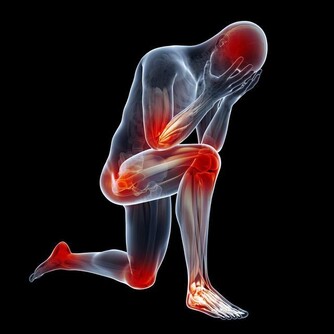

膝蓋退化別擔心,快喝養膝茶飲!

●膝蓋退化了沒!中醫師蔡曜鍵教你自行檢測,還要提供養膝茶飲!還 不快抄起來。